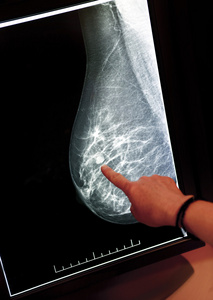

乳腺结节乳房的 x 射线照片